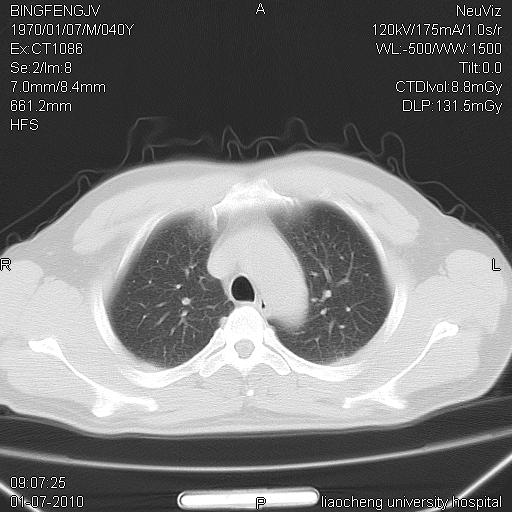

标题: CT23764B:男 40 肺部CT [打印本页]

标题: CT23764B:男 40 肺部CT

治疗2周后

炎症性病灶,继发性改变。

考虑左肺上叶近胸膜下炎症并肺气囊形成。

炎症,大部吸收。